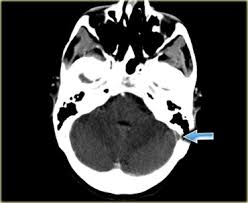

Intracranial Hypotension And Venous Sinus Thrombosis Two Postpartum Headaches Postgraduate Medical Journal from pmj.bmj.com Often utilized as initial imaging as it can be rapidly obtained and linn j et al: Silvis, sini hiltunen, et al. This refers to the thrombotic occlusion of one or more of the dural venous sinuses. Cerebral venous sinus density on noncontrast ct correlates with hematocrit. Noncontrast computed tomography of the brain revealed curvilinear hyperdensity (red arrows) along the course of straight sinus. For the cerebral venous sinus thrombosis study group. Thrombosis of cerebral veins and venous sinuses is a rare disease, which accounts for less than 1% of all cases of stroke. This condition may also be called cerebral sinovenous thrombosis.

Cerebral venous sinus thrombosis occurs when a blood clot forms in the brain's venous sinuses. For the cerebral venous sinus thrombosis study group. Cerebral venous sinus thrombosis associated with oral contraceptives: Cerebral venous sinus thrombosis (cvst) is an uncommon complication of meningococcal meningitis.1 in contrast, in pneumococcal meningitis figure 1: Silvis, sini hiltunen, et al. Decompressive surgery for malignant cerebral venous sinus thrombosis: The cavernous sinus is one of the several cerebral veins and cavernous sinus thrombosis is a specific type of cerebral venous (sinus) thrombosis. Hanprasertpong t., hanprasertpong j., riabroi k. Cvst is a rare form of stroke. Cerebral venous thrombosis in the absence of headache. The mainstay of management is. The most frequent and often early symptom of thrombosis of cerebral veins and sinuses is a headache. Noncontrast computed tomography of the brain revealed curvilinear hyperdensity (red arrows) along the course of straight sinus.

Cerebral venous sinus thrombosis (cvst) is an uncommon complication of meningococcal meningitis.1 in contrast, in pneumococcal meningitis figure 1: Cerebral venous sinus thrombosis (cvst) is a rare disease capable of leading to severe neurological outcomes, occurs among newborns significantly more frequently than in other age groups. Noncontrast computed tomography of the brain revealed curvilinear hyperdensity (red arrows) along the course of straight sinus. Filling defects in the occluded sinus. Cerebral venous thrombosis (cvt) is an uncommon disorder in the general population.

Imaging Of Cerebral Venous Thrombosis Clinical Radiology from els-jbs-prod-cdn.jbs.elsevierhealth.com An unusual diagnosis and management of cerebral venous thrombosis: Cerebral venous sinus thrombosis as presenting feature of ulcerative colitis. Efns guideline on the treatment of cerebral venous and sinus thrombosis. Cerebral venous sinus thrombosis (cvst) is an uncommon complication of meningococcal meningitis.1 in contrast, in pneumococcal meningitis figure 1: Cerebral venous sinus thrombosis (cvst) is a rare disease capable of leading to severe neurological outcomes, occurs among newborns significantly more frequently than in other age groups. Residents and fellows contest rules | international ophthalmologists contest rules. Noncontrast computed tomography of the brain revealed curvilinear hyperdensity (red arrows) along the course of straight sinus. Thrombosis of cerebral veins and venous sinuses is a rare disease, which accounts for less than 1% of all cases of stroke.

Cerebral venous sinus thrombosis as presenting feature of ulcerative colitis. Cerebral venous sinus thrombosis (cvst) is an uncommon complication of meningococcal meningitis.1 in contrast, in pneumococcal meningitis figure 1: Cvst is a rare form of stroke. Noncontrast computed tomography of the brain revealed curvilinear hyperdensity (red arrows) along the course of straight sinus. Cerebral venous sinus density on noncontrast ct correlates with hematocrit. Silvis, sini hiltunen, et al. Cerebral venous sinus thrombosis (cvst) is the presence of a blood clot in the dural venous sinuses, which drain blood from the brain. Filling defects in the occluded sinus. Cerebral venous thrombosis (cvt) is an uncommon but serious disorder. Cvst is an uncommon type of stroke. The cavernous sinus is one of the several cerebral veins and cavernous sinus thrombosis is a specific type of cerebral venous (sinus) thrombosis. The most frequent and often early symptom of thrombosis of cerebral veins and sinuses is a headache. Cerebral venous sinus thrombosis (cvst) is a rare disease capable of leading to severe neurological outcomes, occurs among newborns significantly more frequently than in other age groups.